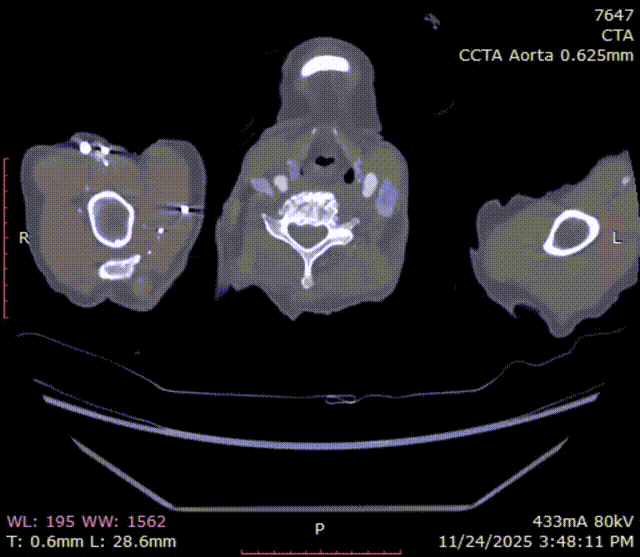

术前CTA

术前CTA可见,患者解剖复杂,Ⅲ型弓,偏心型弓部动脉瘤。

斑马导丝是治疗什么的「胸有乾坤」至简至易 行之有效—— Zone 0 TBE植入治疗弓部动脉瘤病例报道_https://www.jmylbn.com_新闻资讯_第6张

术前3D重建

测量数据: